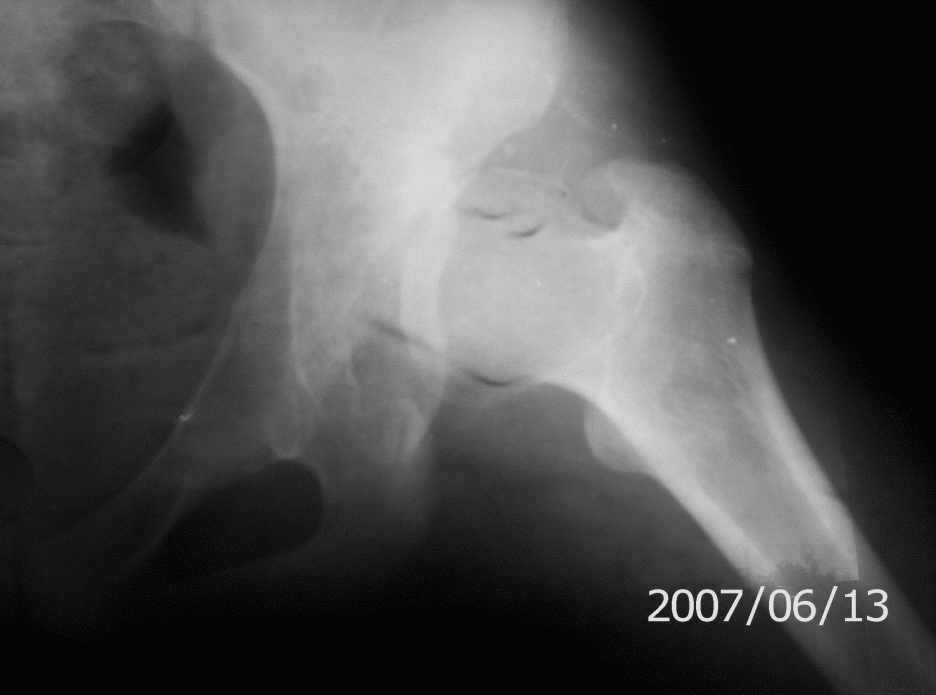

[Ortho] Дисплазия тазобедренного сустава 14 лет

Обратилась девушка 14-ти лет с жалобами на боли в левом тазобедренном

суставе, хромоту.

Лечилась консервативно по поводу врожденного вывиха бедра слева.

Движения в суставе не ограничены, укорочение левой н/конечности на 1.5 см.

Посоветуйте пожалуйста тактику лечения.